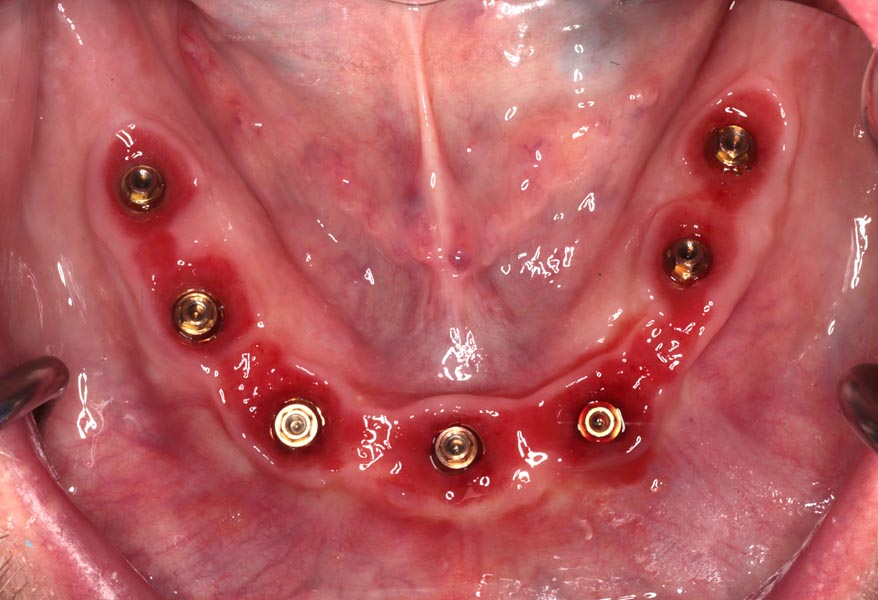

All upper teeth extracted, implants and bone filler placed. Not, we did not remove any bone and attempted to disturb the gums minimally.

Three months post-surgery in the upper, the patient is ready to start the lower. Back, existing implants placed 9 months earlier when we tried to save teeth.

Three months later the patient returns for a series of appointments to fabricate his final prostheses. This is when we note that his homecare is slipping. Notice the redness at the gums that wasn’t seen previously. He was alerted to the issue and educated on how to improve.